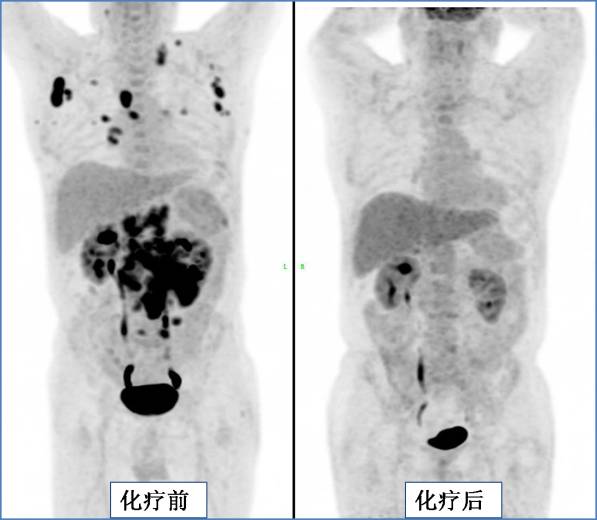

上图为淋巴瘤化疗后病灶完全消失。